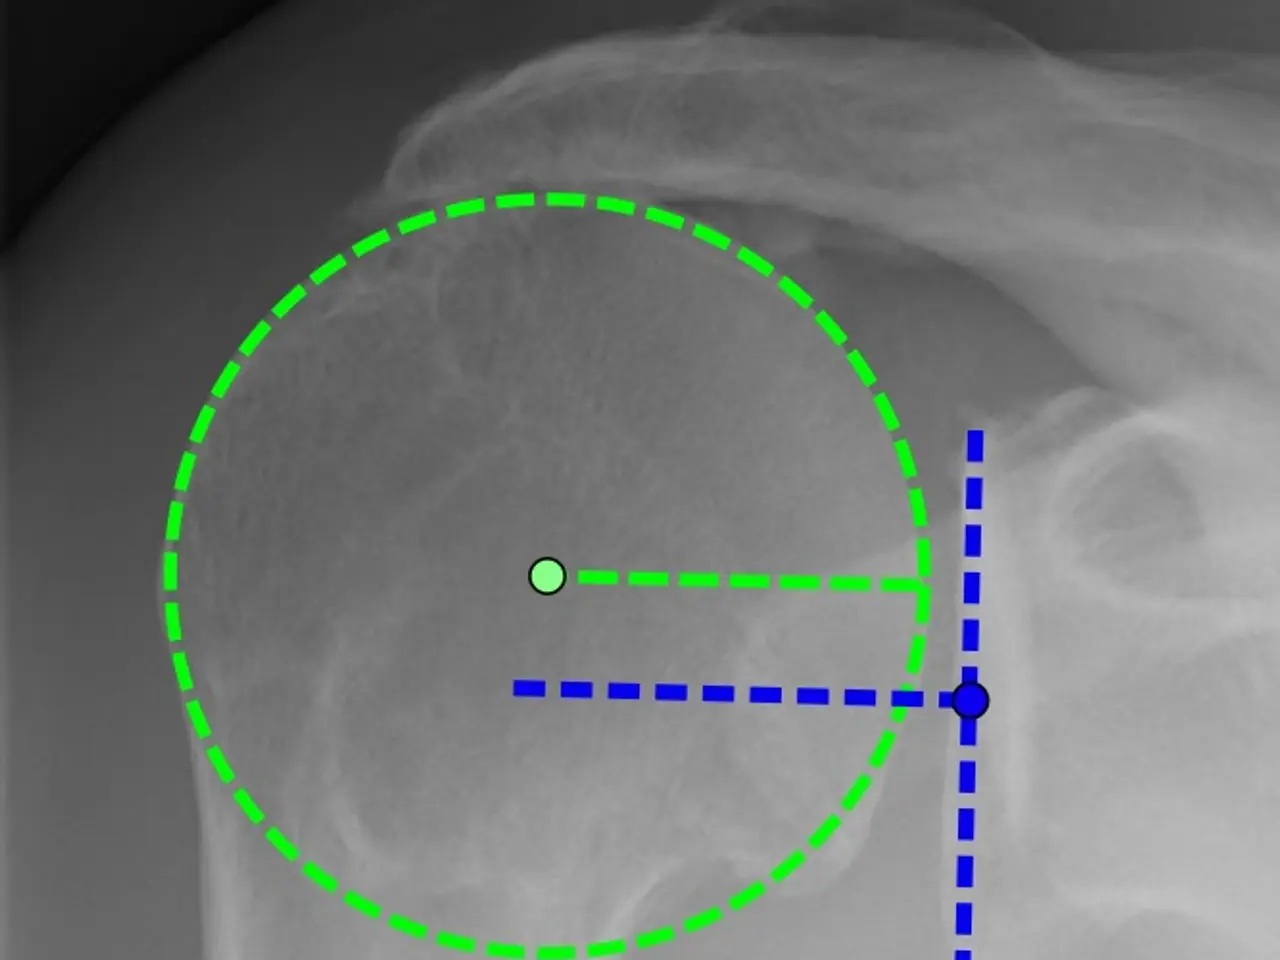

The image shows an x-ray of a man's shoulder with a green circle in the middle, which appears to be a radiograph. The green circle is surrounded by a blue line, indicating the presence of a fracture in the shoulder.